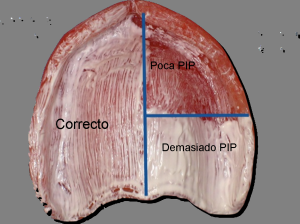

- Evaluar puntos de sobre presión , con pasta indicadora de

presión (PIP), para su correcto uso, observe la imagen derecha,

que muestra la cantidad de pasta necesaria que debe ser aplicada

con un pincel plano.

- En la imagen derecha inferior se observan las superficies de

sobrepresión, que deben ser aliviadas con fresa adecuada